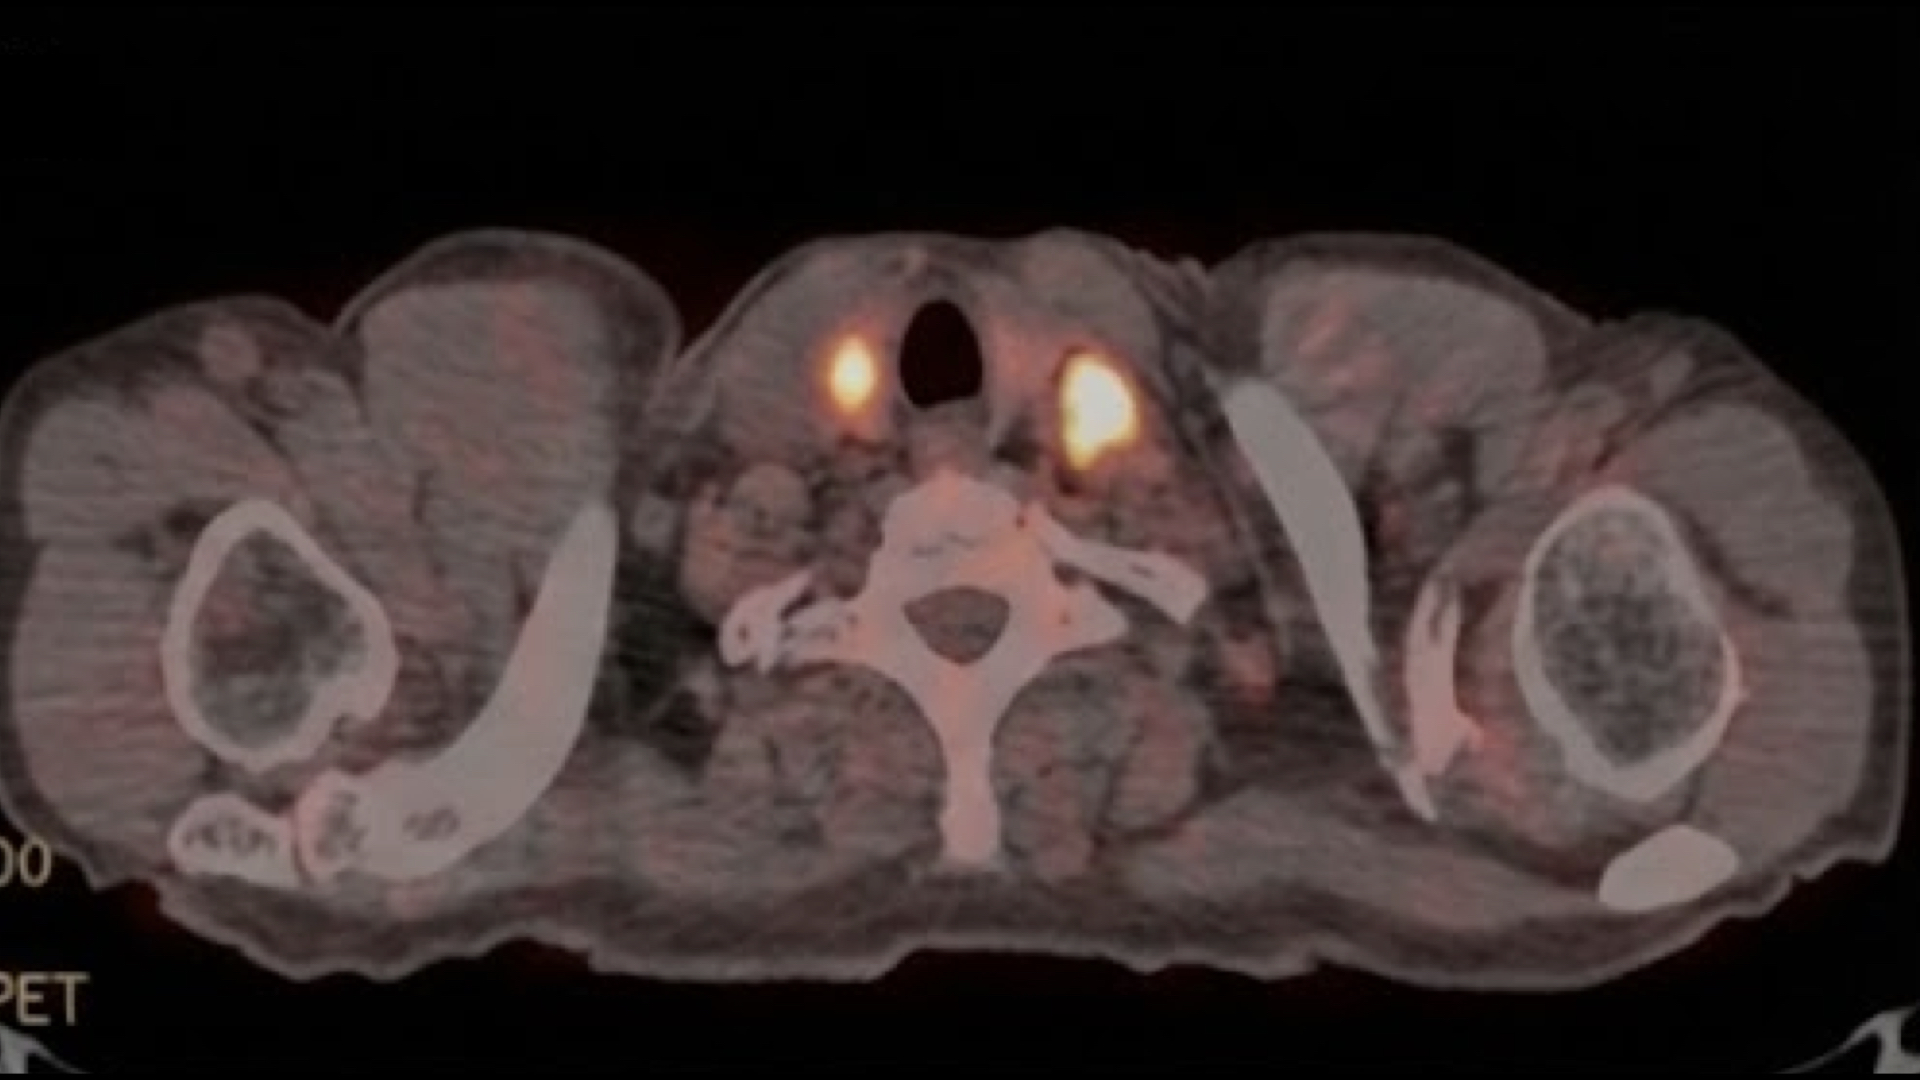

Los ITNs (Nódulos Tiroideos Incidentales) son un hallazgo común en la medicina moderna. En estudios de imagen transversal (TC/RM), la prevalencia en adultos oscila entre el 16% y el 25%. En el caso de la medicina nuclear con 18F-FDG PET-CT, la captación se presenta en el 1-2% de los estudios, pero con una relevancia clínica desproporcionada.

Medicina Nuclear: PET-CT (18F-FDG)

El incidentaloma tiroideo detectado mediante PET-CT es un hallazgo de alta relevancia clínica. La captación focal de glucosa radiomarcada suele correlacionarse con una mayor agresividad metabólica celular.

Criterios de Malignidad Metabólica:

- Captación Focal: Un incidentaloma con captación circunscrita tiene un riesgo de malignidad significativo, reportado entre el 30.8% y 34.6% por Vassallo et al., y hasta un 50% en series de Tappouni et al.

- Ratio SUVmax: Un ratio de SUVmax nódulo/fondo > 2 es un predictor fuerte de malignidad, indicando una tasa de glucólisis desproporcionada respecto al parénquima normal.

Captación Difusa (Signo de Benignidad):

A diferencia de la captación focal, la captación difusa y bilateral de FDG suele estar asociada a actividad autoinmune benigna, típicamente secundaria a una tiroiditis crónica (Hashimoto) en fase activa.

Recomendación: Todo PET-CT positivo focal requiere correlación ultrasonográfica inmediata y probable PAAF según características morfológicas.